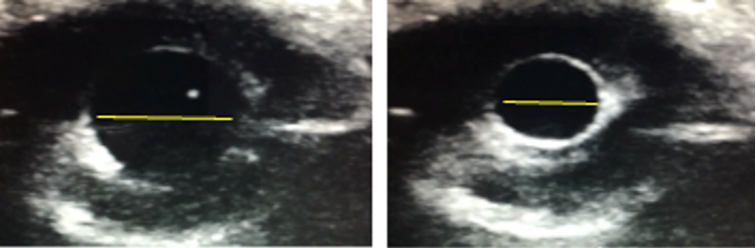

Figure 2a. Normal function seen in the A4C view